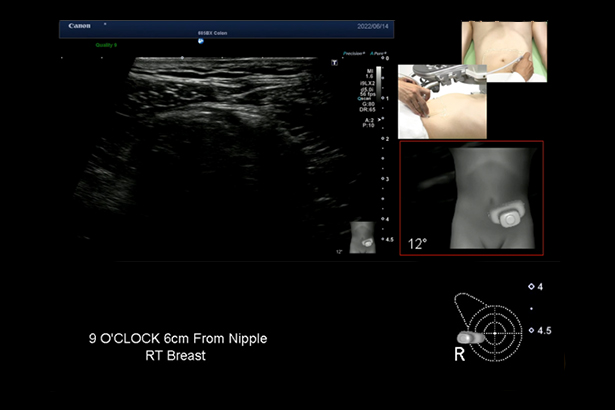

智能體標定位功能,通過磁傳感器獲取探頭物理位置信息,直觀記錄探頭成像位置,幫助介入治療和隨訪的精準定位。